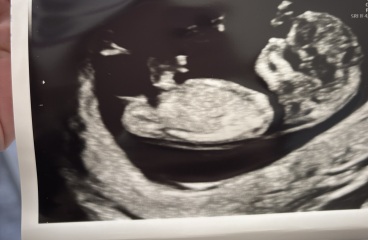

I had my 12 week scan yesterday and I feel like the forehead in the scan looks abnormal? I have been worrying since. The person who did the ultra sound didn’t say anything but it doesn’t look round and like anyone else’s scan I have seen

Is my scan normal?

Looks normal to me

They scan baby at all different angles which I think can distort the shape that you see on the print out. They would have said something if they were concerned, especially where the head and brain is concerned.